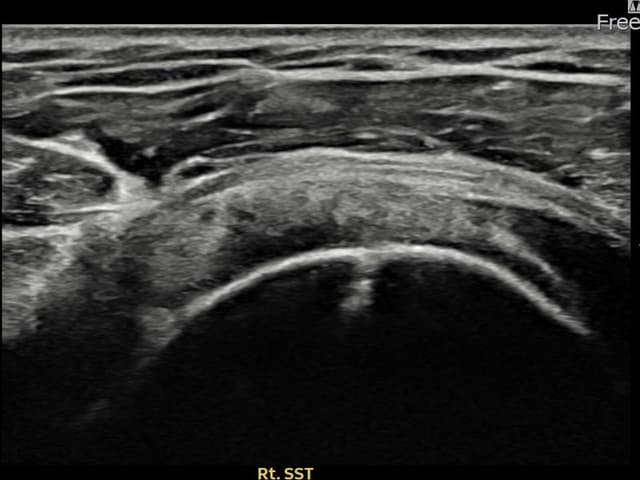

[촬영시기:23.09.19~23.11.21]

[어깨인대 축소봉합술] 우측 어깨 통증과 야간 통증으로 수면 장애가 있어 내원하셨습니다.